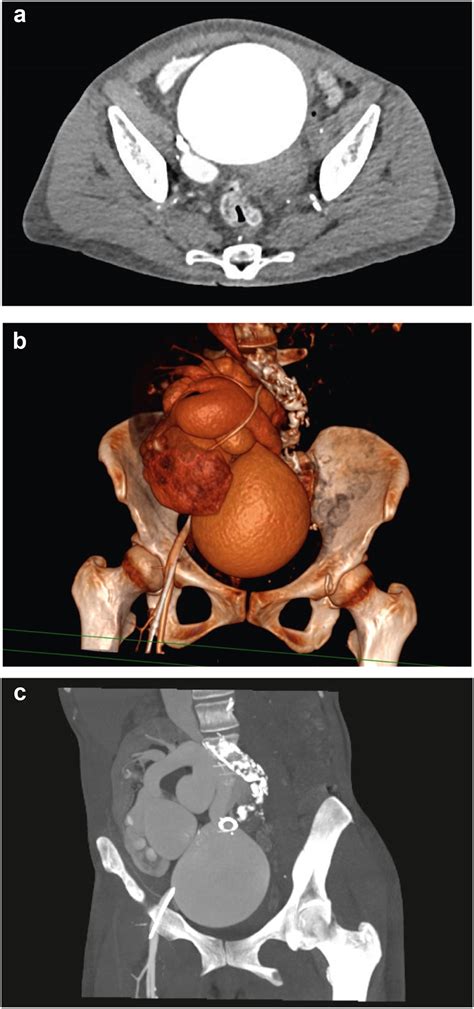

• Arteriovenous (AV) Fistulas: Abnormal connections between arteries and veins allow blood to bypass capillary beds, creating a massive drop in systemic vascular resistance.

• Catheterization: Used in cases where an AV fistula is suspected, allowing clinicians to measure oxygen saturation in different vessels.

Unlike standard heart failure, where treatment focuses on supporting the heart muscle with neurohormonal blockade, the treatment of High Output Heart Failure is strictly aimed at the underlying etiology. For example, if the cause is severe anemia, blood transfusions or hematinic therapies are the primary interventions. If the cause is an AV fistula, surgical or endovascular closure of the fistula is required to restore normal hemodynamic stability. Managing these underlying conditions often allows the heart to revert to normal function without the need for long-term cardiac medications.